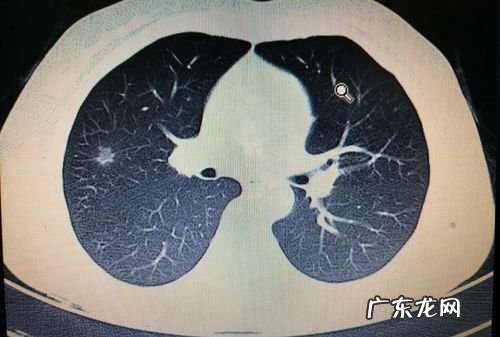

发现肺部小结节怎么办肺部小结节这种疾病很难确诊,一直是医学难点 。当我们发现肺部小结节时,必须要重视起来才行 。下面我给大家讲一讲,得了肺部小结节怎么办 。

3.肺部结节临床较常见,主要可能的因素包括结核、炎症性病变以及肿瘤等 。我们可以先做一个CT检查,然后看影像学特点进一步判断 。